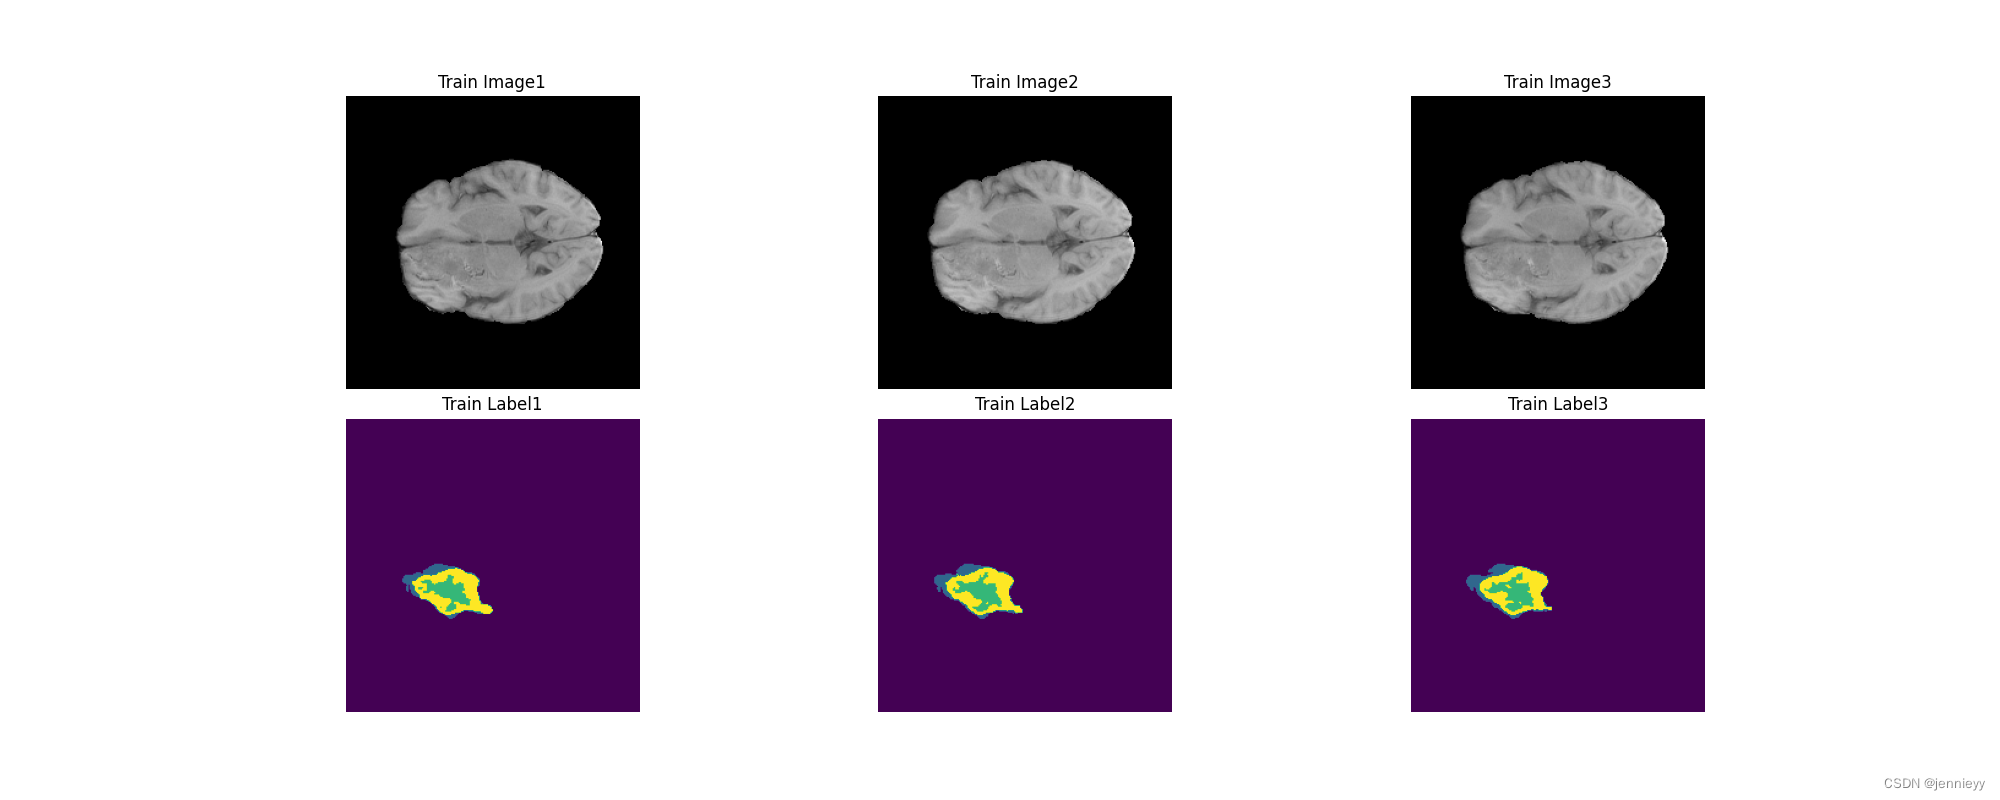

Dataset Visualization

At this stage it is useful to examine the training and testing data.